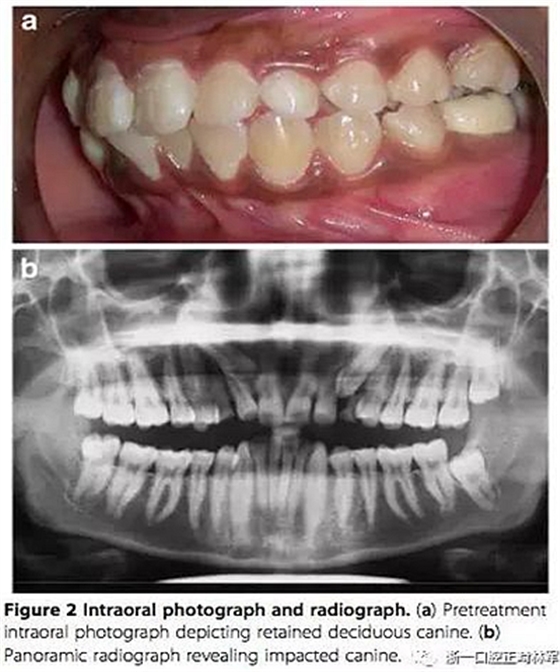

患者女,16歲,主訴:下牙列擁擠。

左上乳尖牙未脫落,全景片示左上尖牙頰側(cè)阻生。